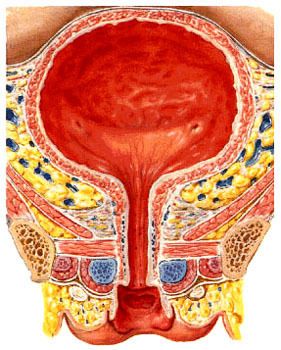

尿路结石是泌尿系统各部位结石病的总称,是泌尿系统的常见病。根据结石所在部位的不同,分为肾结石、输尿管结石、膀胱结石、尿道结石。本病的形成与环境因素、全身性病变及泌尿系统疾病有密切关系。其典型临床表现可见腰腹绞痛、血尿,或伴有尿频、尿急、尿痛等泌尿系统梗阻和感染的症状。

结石进入输尿管时,常停留或嵌顿于生理狭窄处,即肾盂输尿管联接处、输尿管跨越髂血管处及输尿管膀胱联接处。由于输尿管内径自上而下由粗变细,结石位于输尿管下1/3处最为多见。